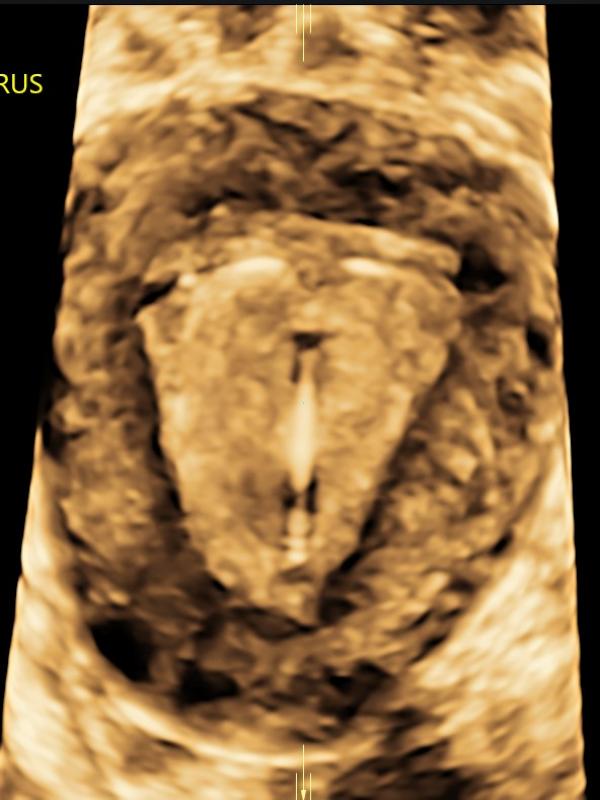

Female pelvic/gynecologic ultrasound

A provider may order a pelvic ultrasound for a number of reasons. Some common reasons are: pelvic pain, irregular bleeding, lack of periods or fertility assessment. Ultrasound has proven to be an important diagnostic tool in evaluating the gynecologic patient. With improved technology, ultrasound plays an integral role in evaluating the female pelvis. The uterus, uterine lining (endometrium), and ovaries are well-visualized using transabdominal and transvaginal ultrasound imaging.

Female pelvic/gynecologic ultrasound FAQ

• What should I expect during this exam? Typically, your provider will order a transabdominal and transvaginal ultrasound to evaluate the uterus, uterine lining and ovaries. Transabdominal (ultrasound performed by placing the transducer on the skin of the lower abdomen). Transvaginal (ultrasound performed by placing a cylinder-shaped ultrasound camera into the vagina). Transvaginal ultrasound adds information and is often the preferred method of evaluation.

• What is the preparation for a Pelvic ultrasound? Patients are asked to come to the exam with a full bladder. We recommend drinking 24 ounces, finishing 45 minutes before your appointment. You can drink any kind of clear liquid, including pop, tea, juice or water. No milk products, as they do not fill the bladder.

• Who interprets the pelvic exam? Sound Health Imaging contracts with Proscan Reading Services to read our exams. They are fellowship-trained, board-certified radiologists with subspecialty training.

• When and how will I get results? The pelvic exam will be read by the radiologist within 24 hours of your study. The results will be sent directly to your referring provider the week-day after your exam.

• How do I schedule my Pelvic ultrasound at Sound Health Imaging? A provider order is required for a pelvic ultrasound. When you see your healthcare provider, let them know you would like to have your ultrasound scheduled at Sound Health Imaging. Or, after you see your provider, you can call our office and make your ultrasound appointment and then bring your order with you at the time of exam.

• 3D/4D Ultrasounds: The best time in the pregnancy for 3D/4D imaging is between 26 and 30 weeks gestational age. At this time there is plenty of amniotic fluid around the baby. Fluid enhances the images and adequate amniotic fluid around the baby is essential for good 3D/4D imaging. As the baby gets closer to term the amniotic fluid naturally decreases, making it more difficult to get good 3D/4D images. Also, 26-30 weeks is a good time for the 3D/4D because the baby has started to “fill out” and take on some of the features it will have at birth. Before 26-30 weeks gestational age the baby looks more skeleton-like. There are a number of factors that affect the quality of the 3D/4D images. Ideally, the baby is positioned away from the placenta and uterine wall. If the fetal hands, feet or umbilical cord are in front of the face it will result in less than ideal images. In order to have a 3D/4D ultrasound at Sound Health Imaging you must have a referral from your medical provider. During the 3D/4D ultrasound, measurements will be taken to assess fetal growth, but an anatomical survey of the baby will not be done. We require that a previous 20-22 week ultrasound for fetal anatomical surveillance has already been done prior to the 3D/4D ultrasound. 3D/4D ultrasounds are not medically necessary and cannot be billed out to insurance companies. Please contact our office for more information.